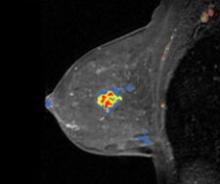

Medrad hopes to thrust new life into molecular imaging with its 510(k) pending FDG-PET power injector system called Intego, designed to promote greater accuracy in dose injection and which reportedly reduces radiation exposure related to FDG-handling by 40 percent.